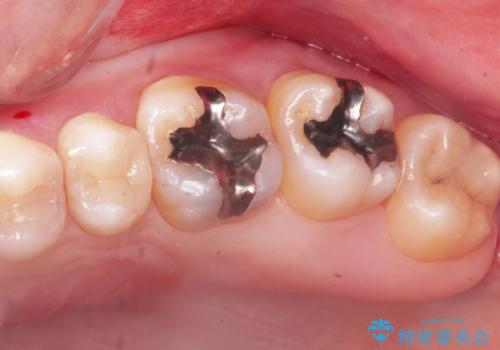

2. 縁下歯石のクリーニングの治療中

2.